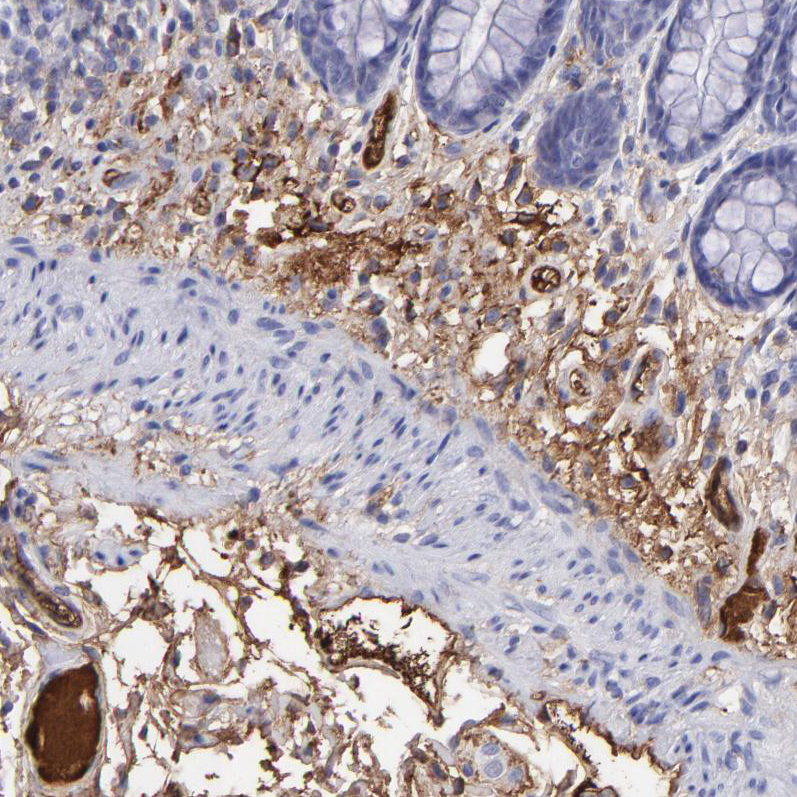

Immunohistochemical staining of human cerebral cortex, liver, placenta and rectum using Anti-FGB antibody HPA001900 (A) shows similar protein distribution across tissues to independent antibody HPA001901 (B).